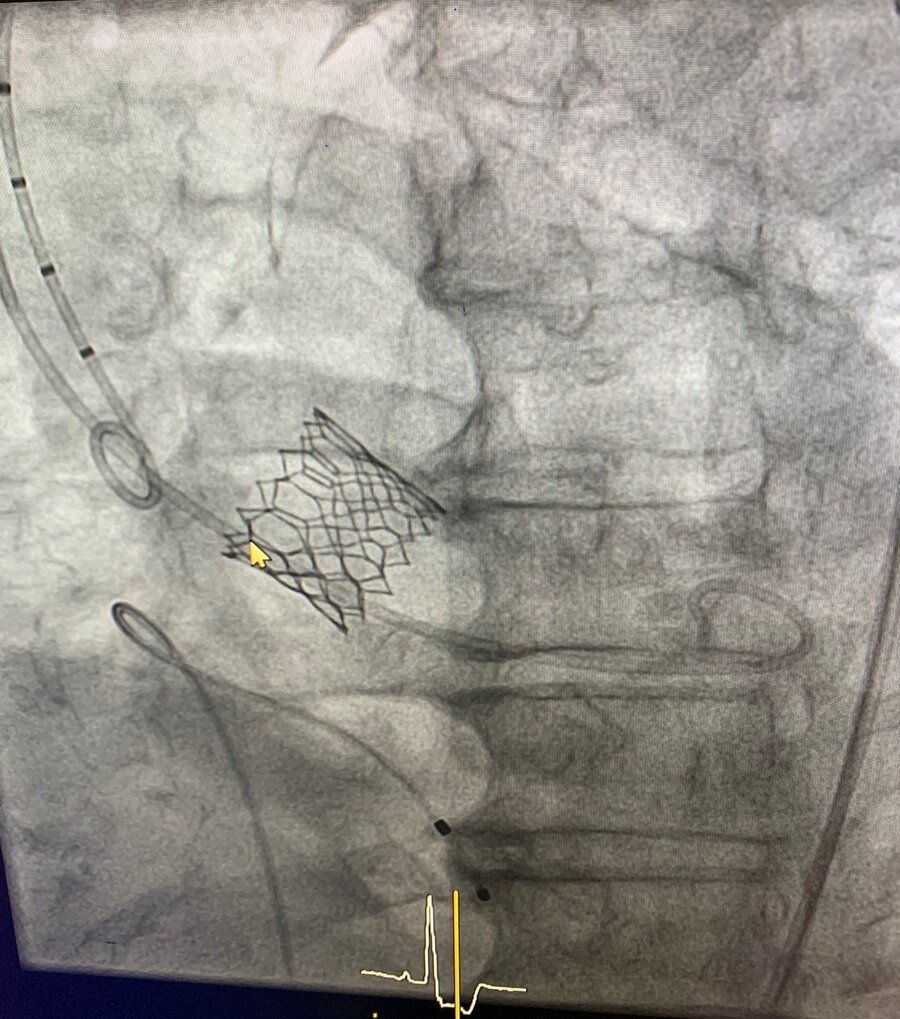

Στις 2/8/2021 στο Αιμοδυναμικό Εργαστήριο της Πανεπιστημιακής Καρδιολογικής Κλινικής του Πανεπιστημιακού Γενικού Νοσοκομείου Αλεξανδρούπολης πραγματοποιήθηκε για πρώτη φορά σε Δημόσιο Νοσοκομείο της Βόρειας Ελλάδας (με εξαίρεση το Νοσοκομείο Παπαγεωργίου στην Θεσσαλονίκη), διαδερμική αντικατάσταση σοβαρά στενωμένης συμπτωματικής αορτικής βαλβίδας από τον Διευθυντή της Πανεπιστημιακής Καρδιολογικής Κλινικής Καθηγητής Καρδιολογίας κ.Δημήτριο Ν. Τζιακά.

Πρόκειται για την περισσότερο απαιτητική επέμβαση στον Τομέα της Καρδιολογίας, η οποία και ολοκληρώθηκε με επιτυχία από τον Καθηγητή Καρδιολογίας ΔΠΘ, Καθηγητή κ. Τζιακά και την υπόλοιπη ιατρική ομάδα της Πανεπιστημιακής Καρδιολογικής Κλινικής.